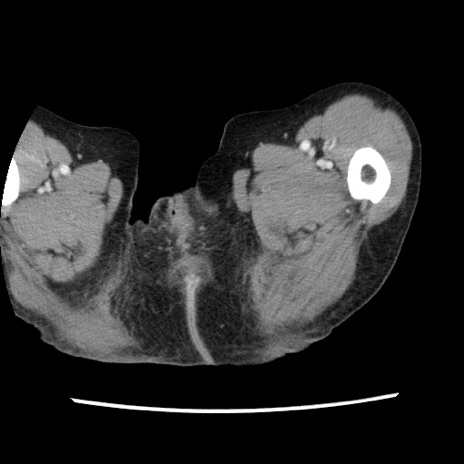

矢状断像

【症例】80歳代女性

【主訴】腹痛

【現病歴】8時間前から腹痛あり来院。

【既往歴】糖尿病、脂質異常症、子宮体癌にて子宮全摘術

【身体所見】意識清明・会話良好だが腹痛で苦悶様、全腹部にわたって反跳痛と圧痛あり

【データ】WBC 13600、CRP 0.14、LDH 224、CK 90